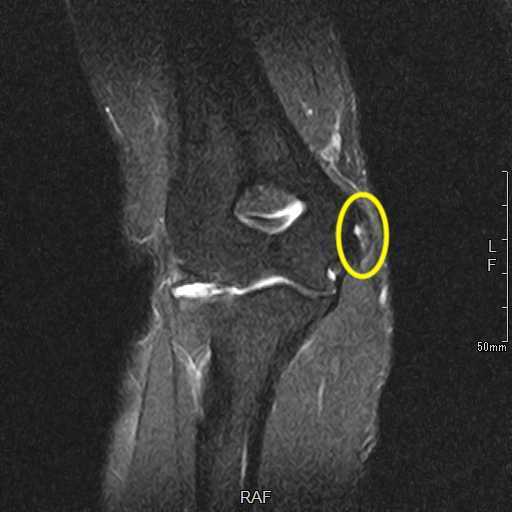

肘離断性骨軟骨炎(野球肘外側型)

肘の離断性骨軟骨炎(以下:OCD:osteochondritis dissecans)は上腕骨小頭という部位に好発することが多いです。

OCDを発見するにはレントゲンや超音波検査で上腕骨小頭軟骨下骨の状態を観察します。

軟骨下骨の不整像が軽微か不明の場合はMRI検査を行いOCDの確定診断を行います。

症例提示

12歳・男性・スポーツは野球(週2回/4年間)

2024年3月頃から外傷誘因なく疼痛出現。

2024年4月上旬、他院受診して超音波検査で軟骨が剝がれていると診断を受けたが経過観察のみ。

2024年5月、当院受診。レントゲン撮影をして離断性骨軟骨炎と診断されてリハビリ開始。

リハビリでは、徒手療法(マッサージ)・運動療法(筋力トレーニング ストレッチ)・物理療法を実施していましたが、

疼痛消失には至らず、組織修復を目的に体外衝撃波を実施しました。

体外衝撃波(拡散型圧力波治療)は、週1回の頻度で3回実施しました。